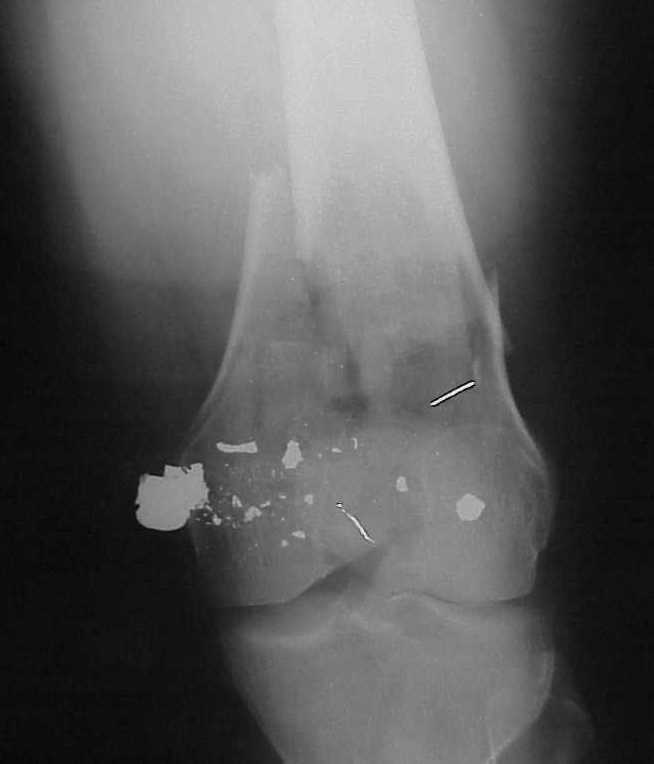

Re: Многооскольчатое бедро

William Obremsky 14 Май 2002, 23:52

> How the screws should be placed?

Use 6.5 mm cannulated screws if you have and

place one anterior to where IMN will go if anterior cortex if insufficient and AP screws on either side of the IMN out of the trochlea to provide some additional varus/valgus stability. I worry about the leg going into valgus w/the lack of lateral cortex.

See attached case that was done several years ago before LISS. He had comminuted trochlea and anterior blocking screws were used to prevent anterior IMN cut-out.